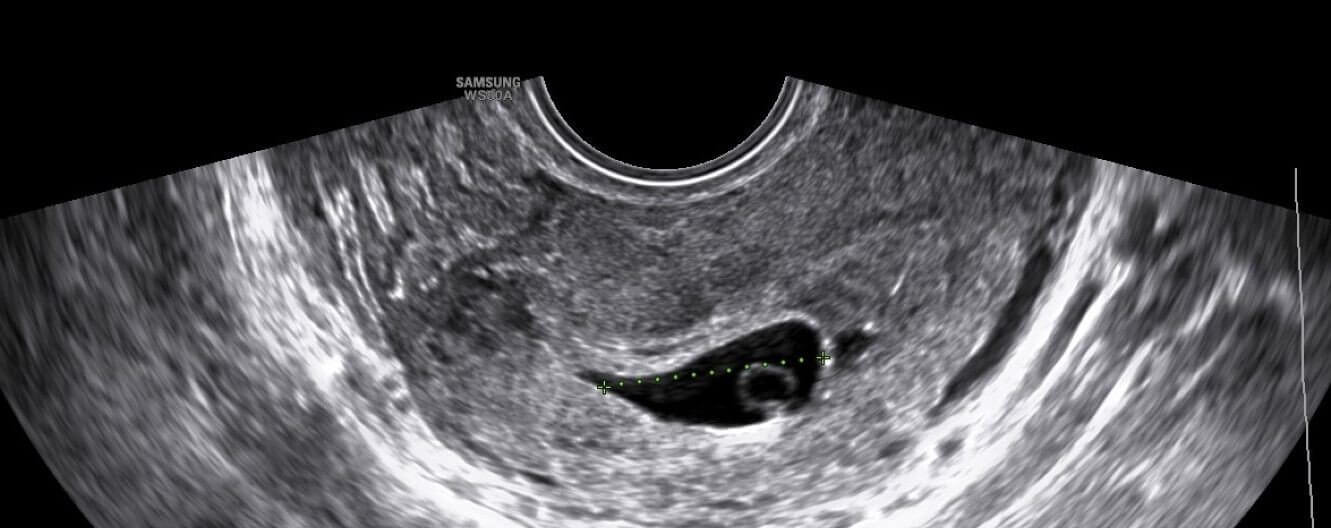

It is the parents’ responsibility to love, care and provide for their children – those already in the world and those yet to be born. But, if a pregnant woman knows there is no way for her to give her child-to-be the physical, emotional and financial sustenance he or she needs to survive and thrive, or if the fetus is diagnosed with a life-limiting medical condition, many believe that it is the mother’s right and obligation to make a very adult decision. This includes taking responsibility and preventing the unborn child from having a life of pain, suffering, sadness and neglect. It is far easier to continue with a pregnancy than it is to supply a living child with everything he or she requires. In fact, it may be more responsible in such a case, and especially in cases of rape, to terminate the pregnancy than it would be to remain with child.

Women who undergo abortions can experience medical complications later on in life. A study published in 2003 by the International Journal of Epidemiology estimated that roughly 15% of spontaneous miscarriages taking place during the first trimester of pregnancy occur in women who previously underwent induced abortion. An abortion can also double the risk of ectopic pregnancies and can increase the prevalence of pelvic inflammatory disease and the incidence of breast cancer.